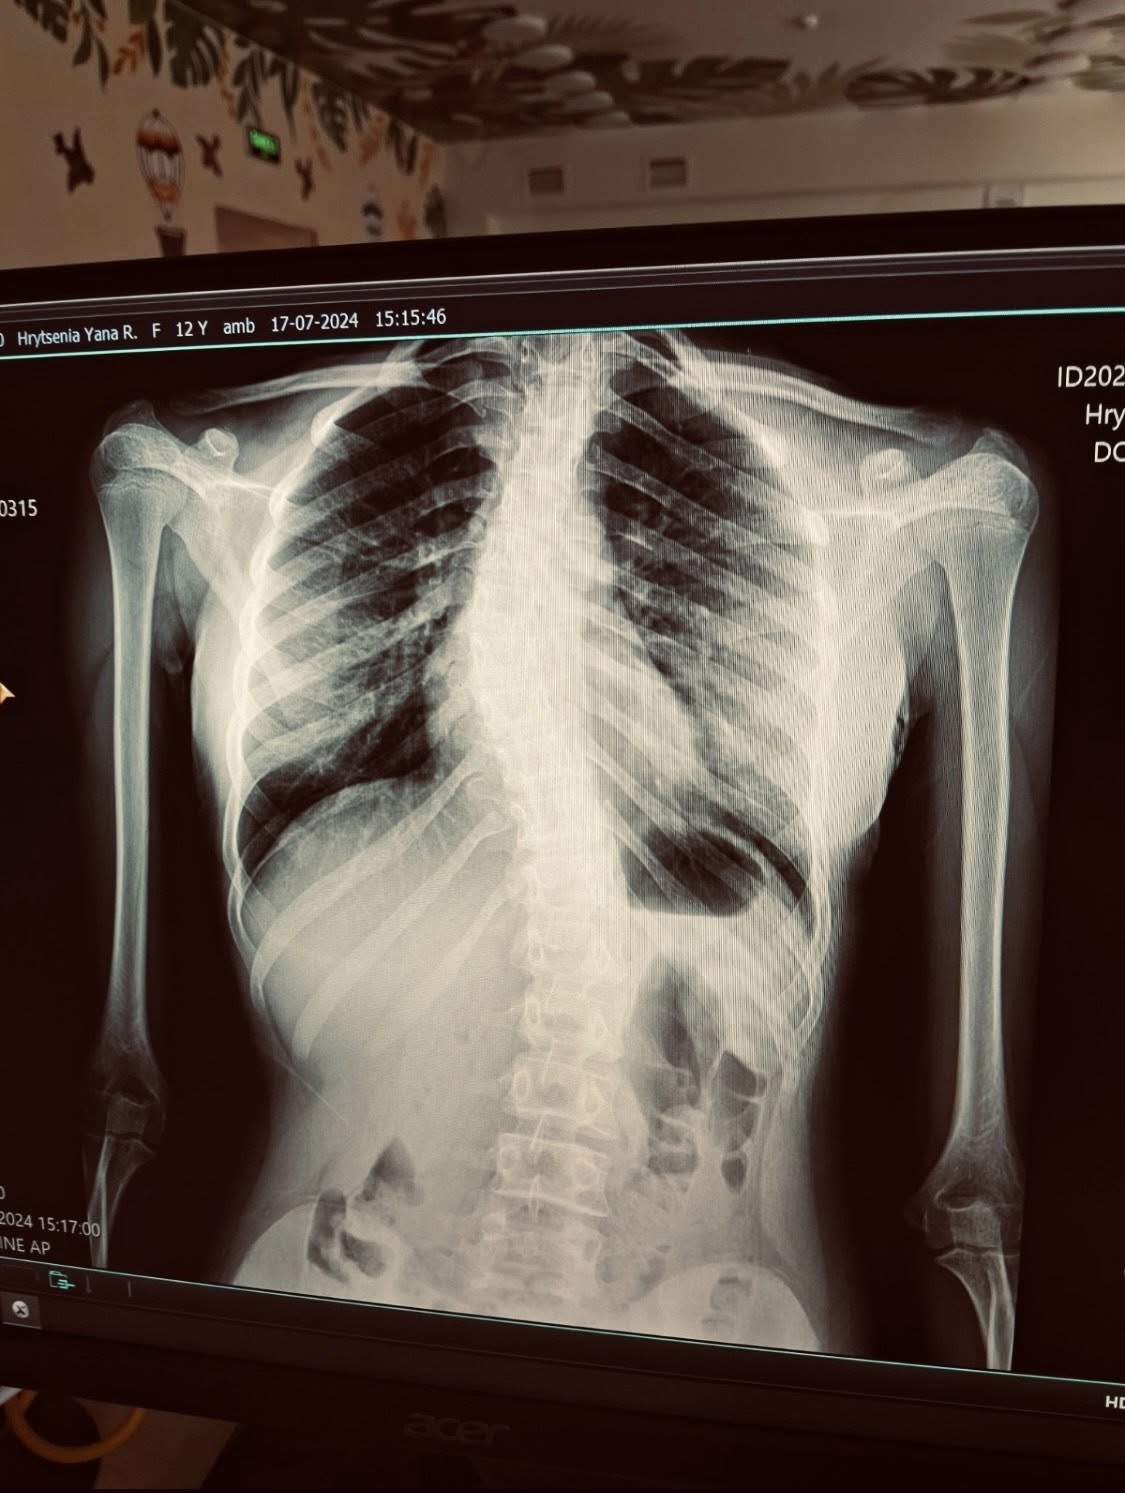

💪 У своєму затишному кабінеті Яна щодня допомагає пацієнтам відновлювати рух після травм та операцій, повертаючи легкість у спині та суглобах. Її арсенал включає сучасні тренажери, такі як тренажер Бубновського та дошка Євмінова, що дозволяють ефективно працювати над оздоровленням. Деякі клієнти звертаються за полегшенням болю, тоді як інші прагнуть зміцнити тіло, щоб уникнути майбутніх проблем із хребтом. Яна завжди розробляє індивідуальні програми, адже її головний принцип: «Головне – дати людині відчути власні сили й повернути впевненість у своєму тілі». Цей підхід робить її роботу унікальною.